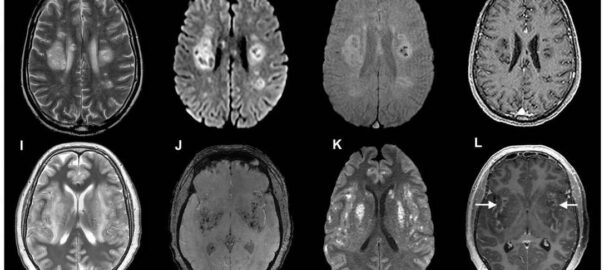

Imagens cerebrais de pacientes com coronavírus, de um estudo publicado em julho. Alguns desenvolvem complicações neurológicas graves, incluindo danos nos nervos. Foto: Ross W. Paterson, Rachel L. Brown, et al. / Imprensa da Universidade de Oxford / via NYT

Os cientistas usaram imagens e avaliaram os sintomas dos pacientes para inferir efeitos sobre o cérebro.

Zandi e seus colegas publicaram uma pesquisa anterio,r em julho, que já mostrava como alguns pacientes com Covid-19 desenvolvem complicações neurológicas graves, incluindo danos nos nervos.